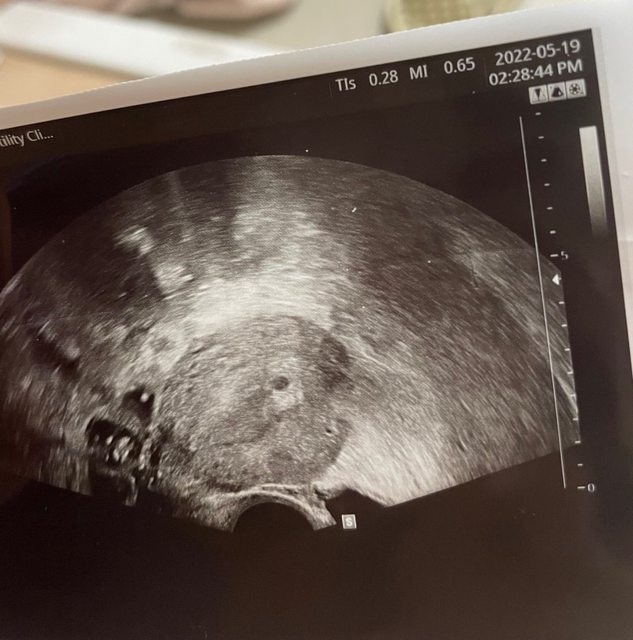

超音波照片 https://i.imgur.com/Opkl8pz.jpg

https://i.imgur.com/sf6Ccue.jpg